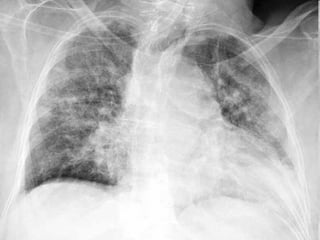

Lab. Dx. of PneumoniaLab. Dx. of Pneumonia

โ€ข CXRCXR

Pneumococcal pneumoniaPneumococcal pneumonia

R upper lobe consolidationR upper lobe consolidation